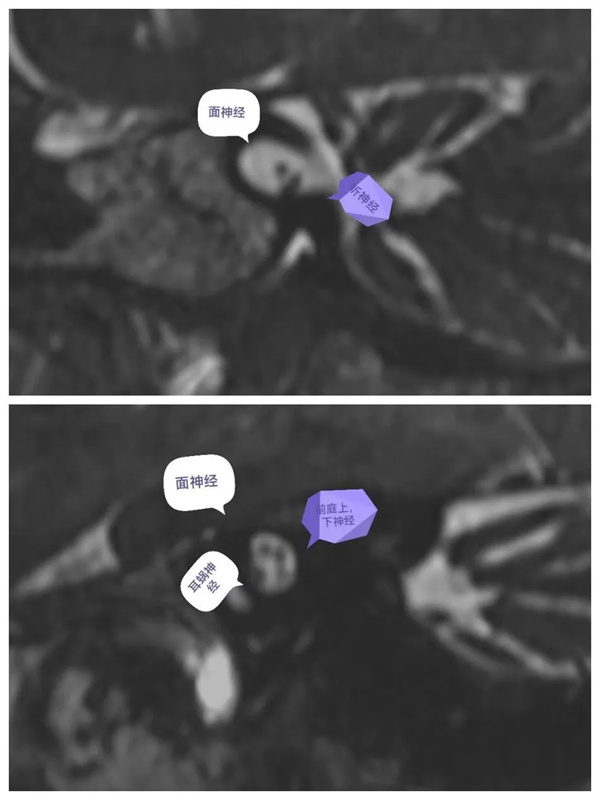

圖6:MIP圖,完美顯示雙側(cè)內(nèi)耳解剖輪廓。

圖7:VR圖,雙側(cè)內(nèi)耳解剖輪廓圖的不同角度顯示圖(后面觀,前面觀,上面觀)。